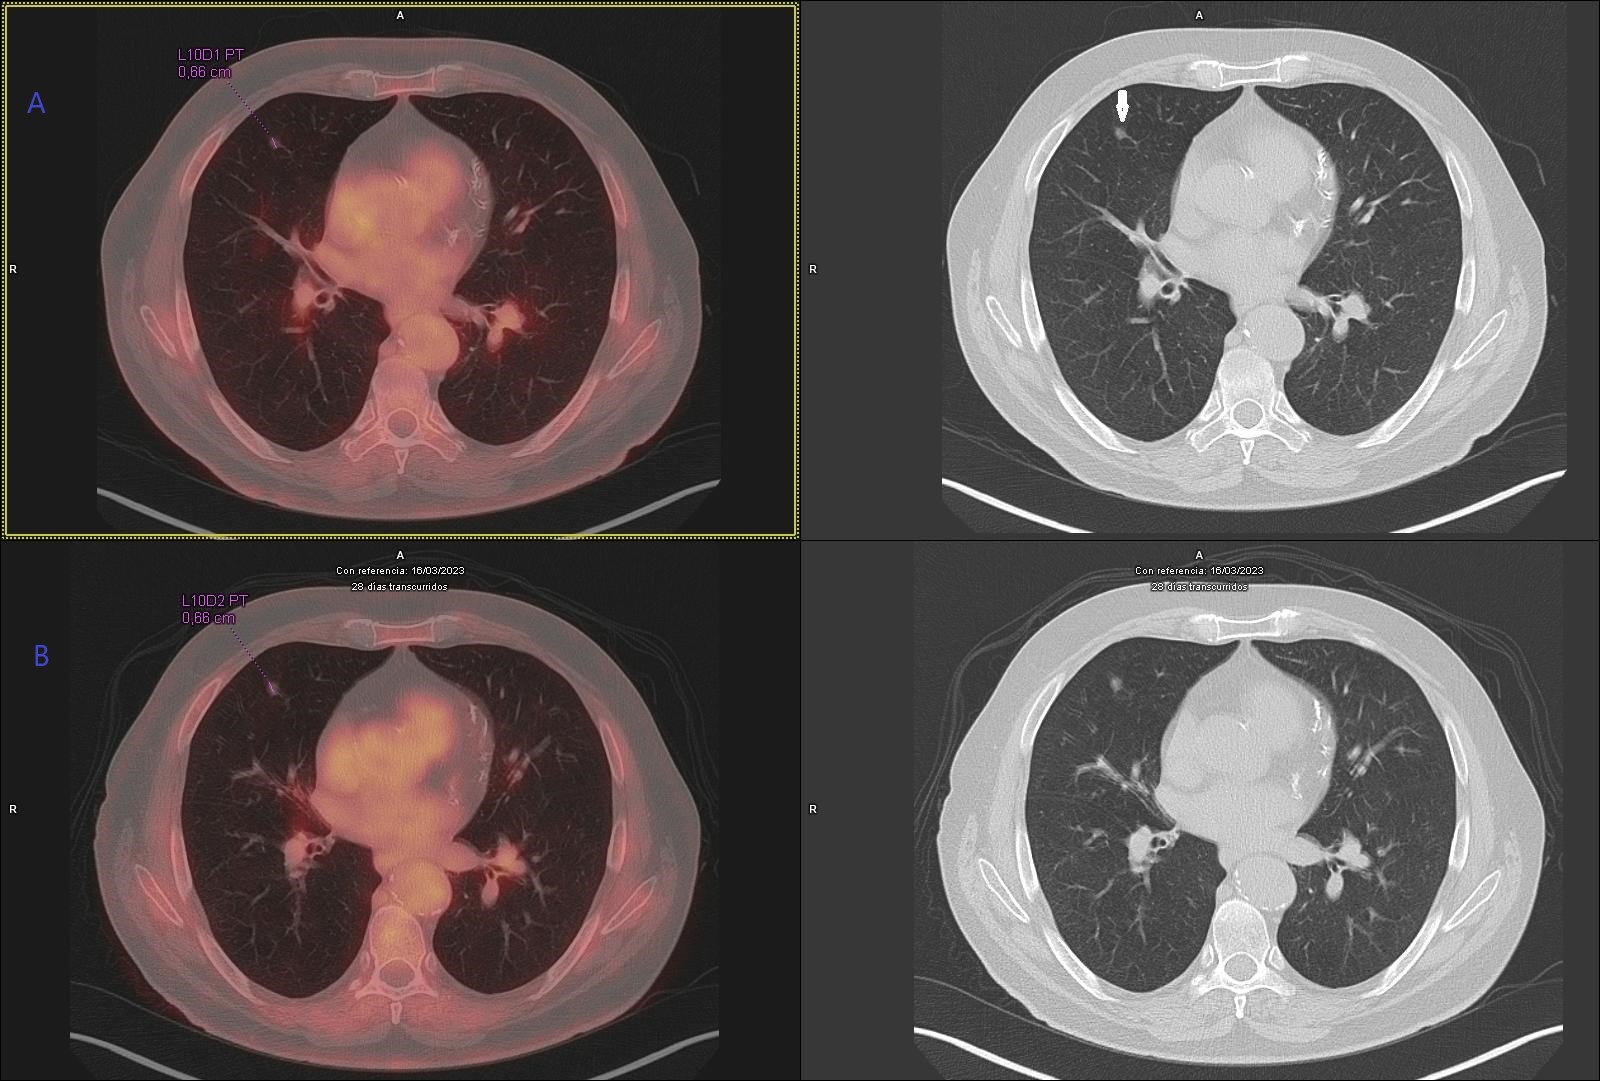

Varón de 74 años, exfumador, con antecedentes de cáncer de próstata tratado mediante radioterapia, ateromatosis generalizada, EPOC, osteoporosis y diverticulosis. En seguimiento por Medicina Interna por dolores óseos generalizados y artralgias, se solicitó PET/TC con 18F-FDG para descartar enfermedad metastásica, ante una resonancia magnética previa que mostraba fracturas vertebrales con edema. No se disponía de otros estudios de imagen recientes. El PET/TC evidenció adenopatías hipermetabólicas en compartimento yugulocarotídeo derecho, en sectores supraclavicular derecho y mediastínicos y un micronódulo pulmonar ametabólico en lóbulo medio (Fig.1.A). Se realizó análisis visual y semicuantitativo con cálculo de SUVmax de las adenopatías (Fig.2.A). Como hallazgos adicionales, se observó extensa calcificación coronaria, concordante con la ateromatosis generalizada del paciente, de interés para la valoración del riesgo cardiovascular. Asimismo, se objetivó aumento del metabolismo en el hemicolon izquierdo (SUVmax= 8,4), sugestivo de afectación inflamatoria, que posteriormente fue confirmada como sigmoiditis crónica en la colonoscopia con biopsia.

Se inició Pembrolizumab 200 mg cada 21 días. El PET/TC tras el primer ciclo mostró respuesta metabólica completa de la afectación ganglionar (Fig. 2 B), persistiendo el micronódulo pulmonar en lóbulo medio sin captación (Fig. 1 B).

Figura 1.B. Estudio de control tras inicio de inmunoterapia: persistencia del micronódulo pulmonar sin cambios morfológicos ni metabólicos.